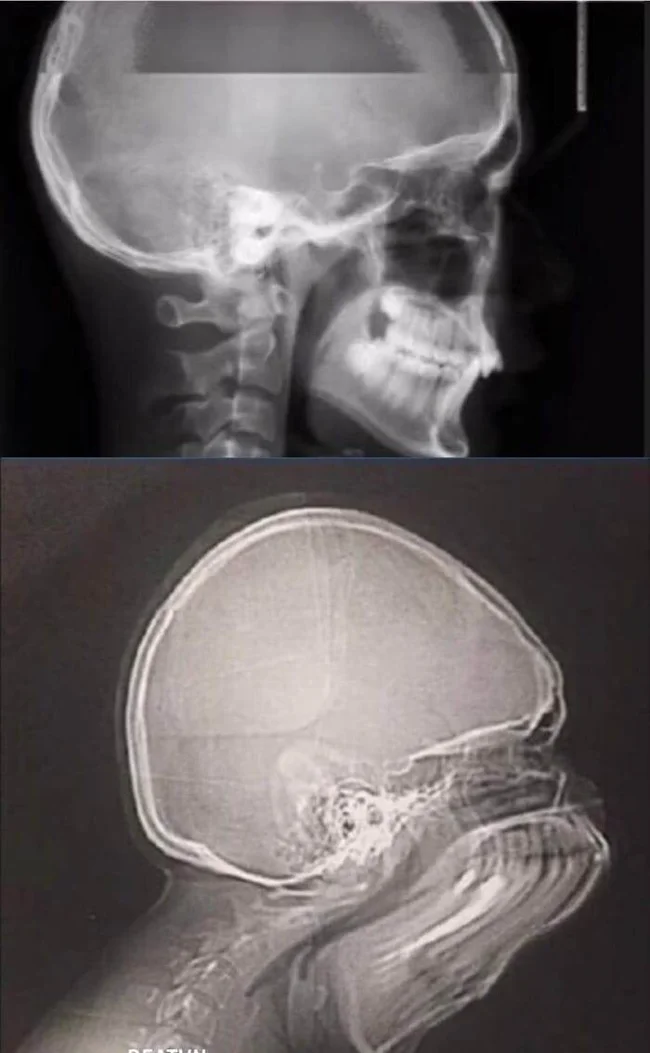

7. Что будет, если чихнуть во время рентгена

8. Победительницы конкурса «Мисс идеальная осанка»